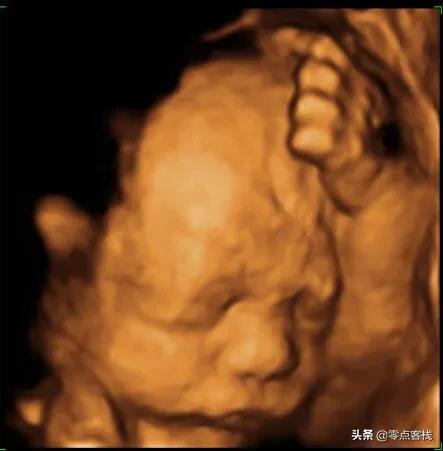

医院里做四维的彩超室门口,永远有两种孕妈妈,一种是做四维彩超一次性就通过的孕妈妈,脸上的喜悦神情是掩盖不住的,还有一种就是做了好几次胎宝宝都不配合的,只能过一会儿重做,特别让孕妈妈们烦恼和焦虑。

在所有的产检项目当中,四维彩超算是相当考验胎宝宝和孕妈妈的配合度的一个检查项目了,因为四维彩超又有“大排畸”的称号,所以医生在给孕妈妈做四维彩超的时候,除了产科彩超常规看的数据,头臀径、双顶径、羊水量、胎心率等,胎宝宝的各个部位都是要扫一遍的,比如胎宝宝的头面部、胸腹部器官、四肢等都是要做一个详细的查看的,如果胎宝宝的胎位不好,背对着或者是趴着,或者胎动不活跃,都会导致四维彩超该检查的部位检查不到,让检查结果没有那么准确了。